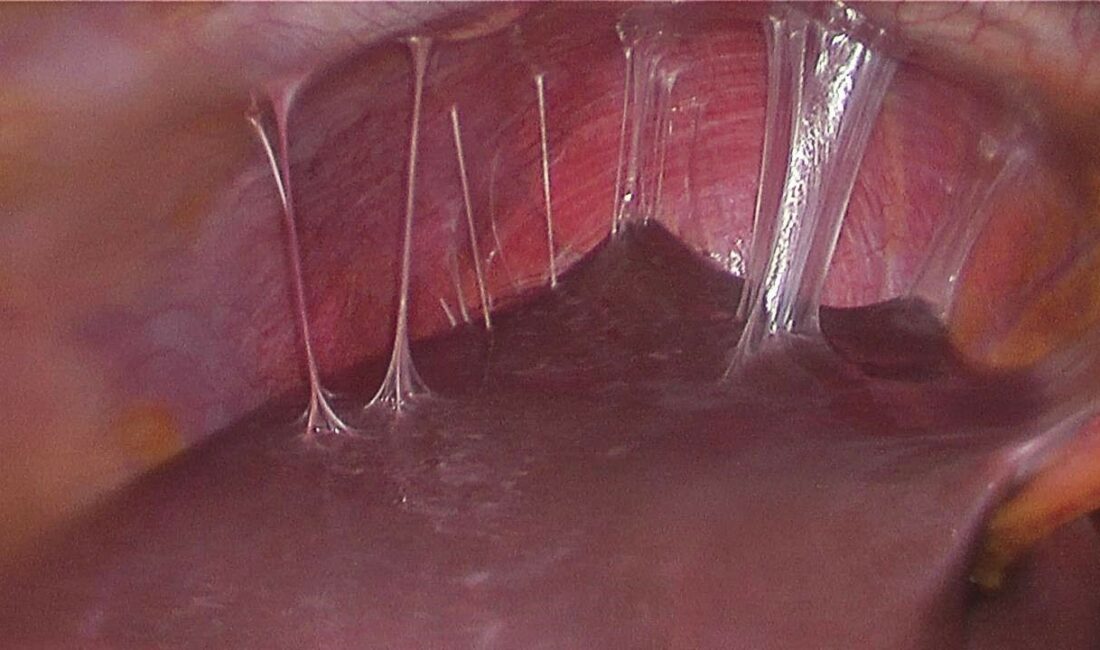

Karın duvarında oluşan defektin, mesh adı verilen bir tıbbi tekstil materyali implante edilerek onarılmasının da bu alanda yapılan en yaygın cerrahi müdahalelerden birisi olduğunu söyleyen Prof. Dr. Esra Karaca, “Bununla beraber, kullanılan meshler ciddi adezyonlara neden olmaktadır. Daha önce fıtık ameliyatı olmuş hastaların yüzde 90’ından fazlasının ameliyat sonrası adezyon semptomları gösterdiği tespit edilmiştir. Adezyonlar ise kronik karın ağrılarına ve iç organlarda ölümcül tıkanıklıklara yol açabilmektedir. Yeni ürünler denenmesine rağmen, post-operatif adezyon henüz başarıyla önlenememiştir. BUÜ Tıp Fakültesi Hastanesi’nden Türkiye ile ilgili bir projeksiyon yapılarak, ülkemizde bir yılda kullanılan fıtık mesh sayısının 100 bin civarında olduğu sonucuna varılmıştır. Bu nedenle; proje çerçevesinde geliştirilecek başarılı bir kompozit meshin, yurt dışından mesh ithalatını önemli oranda azaltacağı öngörülmektedir” dedi.

Karaca ayrıca projede, karın fıtıklarının onarımında kullanılmak üzere çörek otu yağı içeren anti-adezyon özellikli nanolifli yüzey ile takviyelendirilmiş PP örme mesh yapıların geliştirilmesi ve kompozit meshlerin fıtık onarımı ve adezyon önleme performansının in vitro ve in vivo çalışmalarıyla değerlendirilmesini hedeflediklerini de sözlerine ekledi.